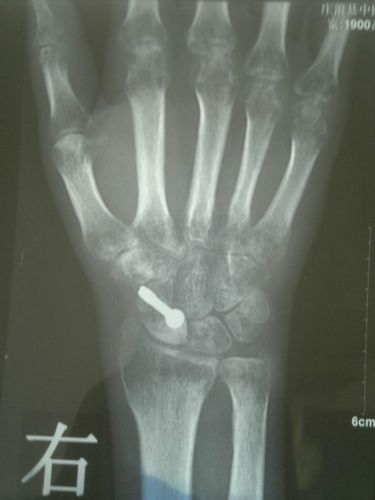

医生,我妈的手腕位置骨折这片子看起来什么

我这骨折严重吗?检查

双手腕关节桡骨粉碎性骨折,做了外固定架手术,(固定架已拆除)现术后80